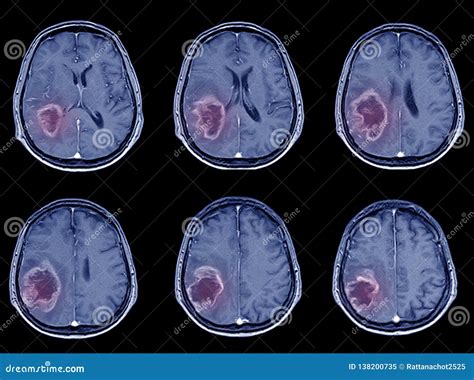

In the early stages of an ischemic stroke , the CT scan might not show a lot of obvious changes. However, there are some subtle signs that experienced radiologists can spot. They look for the following signs:

- Loss of Grey-White Matter Differentiation: The brain is made up of grey matter and white matter, which have different densities. In the early stages of a stroke, the difference between these can become less clear, making it difficult to differentiate between them. This is often the first thing they notice.

- Hyperdense Artery Sign: Sometimes, the CT scan can show a blood clot as a very bright spot in an artery, known as the hyperdense artery sign. This is a telltale sign of a blood clot and helps to confirm the diagnosis.

- Subtle Swelling: The brain tissue may start to swell, and subtle changes in the density of the brain tissue. This can indicate that the brain is not getting enough blood.

Later Signs of Ischemic Stroke on a CT Scan

As time passes, the changes on the CT scan become more apparent. The following signs are usually visible later:

- Hypodensity: Areas of the brain that are damaged due to the lack of blood flow will start to appear darker on the CT scan. This is called hypodensity. It indicates that the brain tissue is dying.

- Mass Effect: As the brain swells, it can push on other structures, causing a mass effect.

- Infarct: This is a term for the area of dead tissue caused by the stroke. It can be seen as a clearly defined dark area on the scan.

Differentiating Ischemic vs. Hemorrhagic Stroke

One of the main goals of the CT scan is to differentiate between an ischemic stroke and a hemorrhagic stroke. A hemorrhagic stroke involves bleeding in the brain. On a CT scan, blood appears bright white. So, if the scan shows any bright white areas, it’s a sign of bleeding. If there’s no bleeding and the scan looks relatively normal (or shows the signs of ischemic stroke ), then it’s most likely an ischemic stroke . This distinction is super important because the treatments for each type of stroke are different.